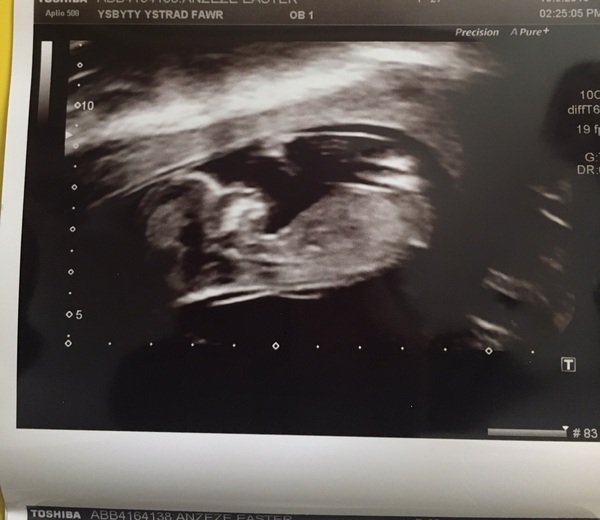

Thanks all! Scan went well, baby is measuring at 10+5 (which matches ovulation) so need to go back in a couple of weeks for nuchal tests etc. Great to see the heartbeat and even little legs kicking when the sonographer pressed down.

Test/scan went well for me too! Baby wouldn't sit still long enough for a good photo but was lovely to see him or her active. EDD. Has been brought forward to 18th Dec.